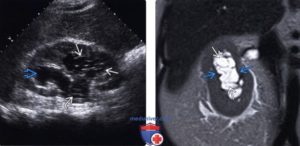

Гиперэхогенные образования — чаще камни. Мелкие белые включения, расположены в чашечках, дают акустическую тень. Имеют округлую или коралловидную форму.

Благодаря ультразвуковой диагностике возможно обнаружить камни размером от 2 мм.

Как выглядит гиперэхогенное образование на УЗИ Если в полости почки, а чаще обеих, обнаруживаются уплотнения большого объема (0,5-1,5 см3), отбрасывающие акустическую тень, они указывают на камни внутри почки.

Объемное образование с фиксируемой тенью может указывать на склерозированный лимфоузел, который образовался после гнойно-воспалительного процесса или в ходе хронического воспалительного заболевания.